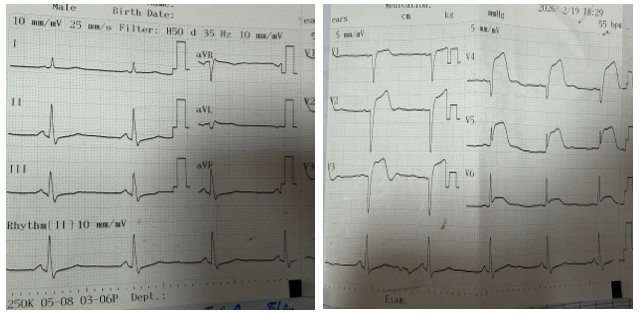

Điện tâm đồ cho thấy ST chênh lên rõ tại V1–V6 (hình 1). Troponin tăng. Creatinine 2,8 mg/dL. Hemoglobin 11,8 g/dL. Tiểu cầu 210 G/L, eGFR 22 ml/phút/1,73 m². Siêu âm tim ghi nhận EF 30%, giảm động nặng vùng trước – mỏm, không có huyết khối thất trái.

Hình 1. Điện tâm đồ lúc nhập viện: Nhịp xoang, tần số 55 lần/phút, ST chênh lên V1-V6 kèm sóng Q hoại tự từ V1-V4